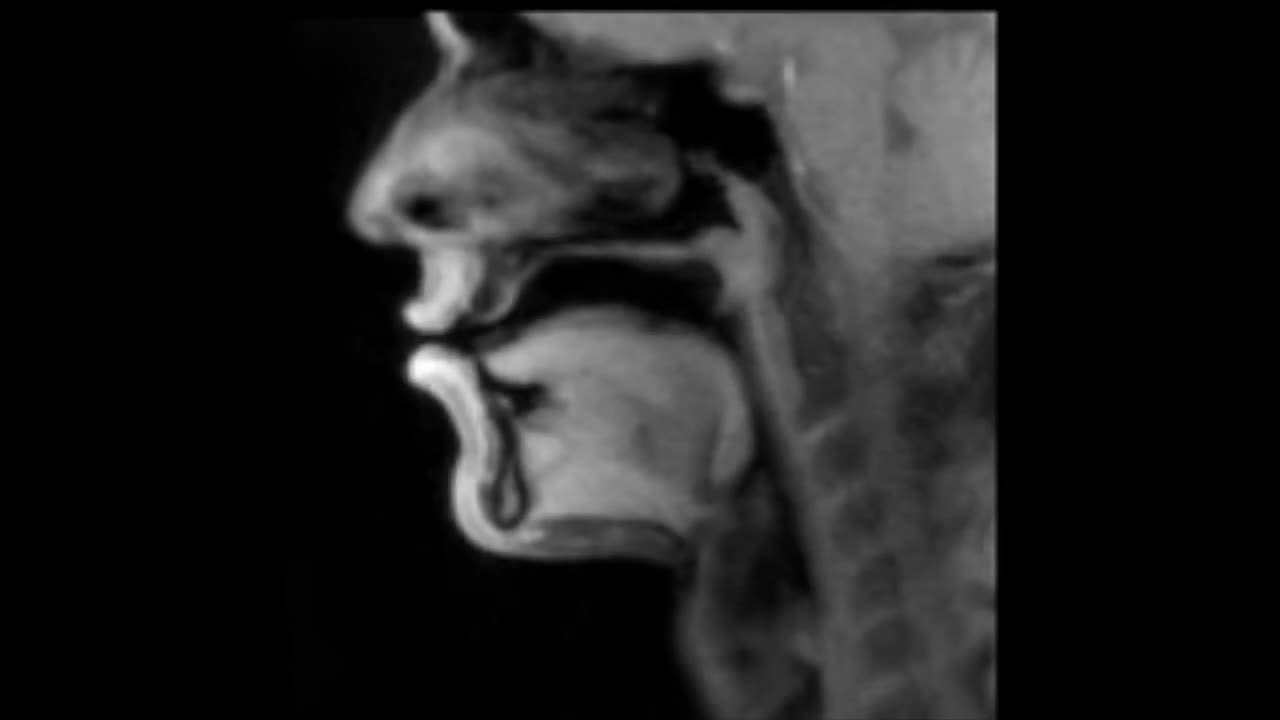

🤯🎙️ This Beatbox Performance Is Happening Inside a Real-Time MRI Scanner! | FeedMyCuriosity

Get ready for the most mind-blowing beatbox performance of the year! Watch as this talented artist raps and beats inside a real-time MRI scanner. What's the most unexpected thing you've ever seen in a medical setting? Share your thoughts in the comments! 👉 To feed your curiosity with more amazing content, make sure you Like & Subscribe! #Beatbox #MRI #MedicalMiracles